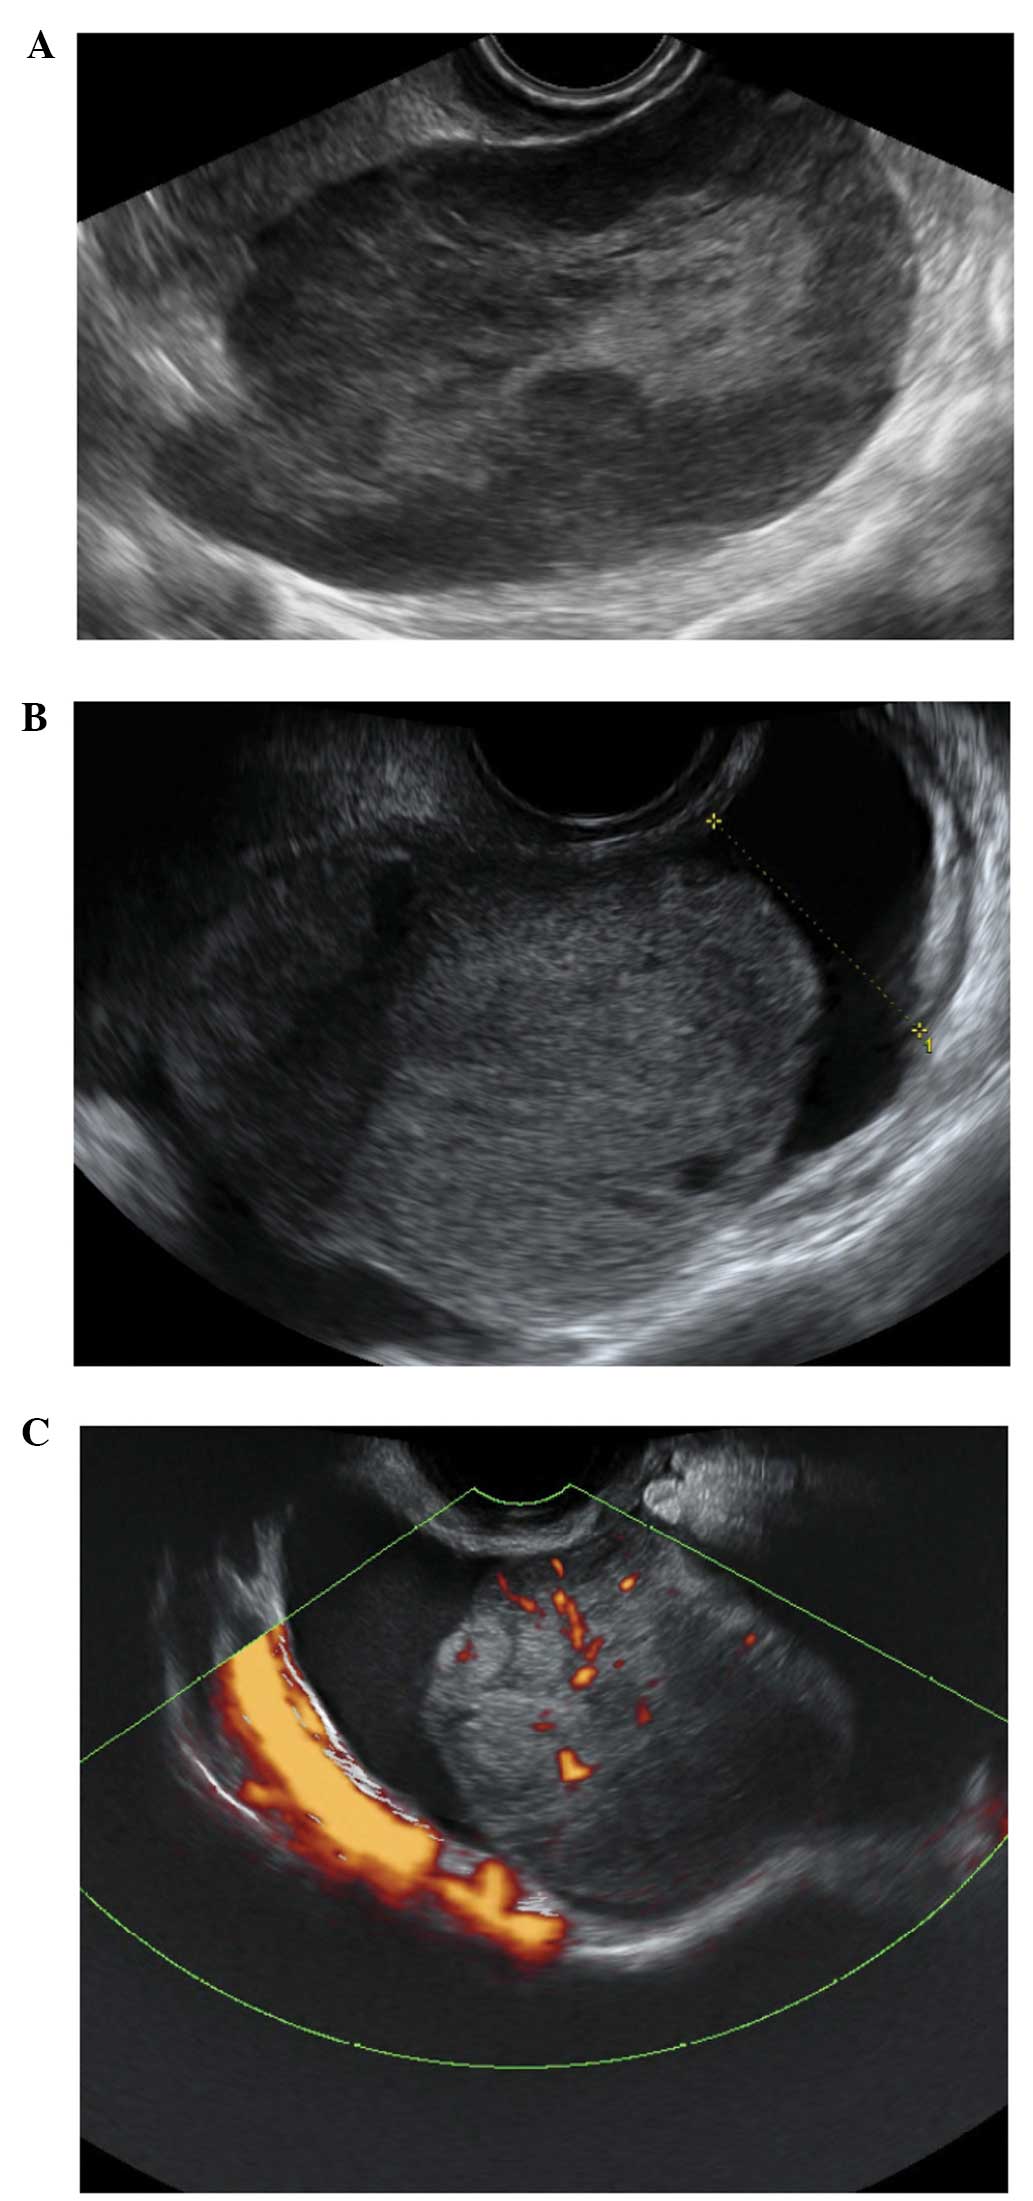

Corpus luteum cysts

These are formed following the rupture of a mature Graafian follicle. They are thick walled hyperechoic cysts that typically demonstrate peripheral circumferential blood flow, sometimes known as the ‘ring of fire’ (12). Some cysts may show areas of internal hemorrhage. The cyst contents typically have a spider-web-like appearance (Fig. 2) due to a small amount of internal hemorrhage, but can frequently show different features including blood clots within the cyst resembling solid components. Doppler examination may be useful in these circumstances as the blood clot will have no blood flow, although perhaps more useful is the a typical jelly-like ‘wobbling’ movement that can be elicited from the blood clot within the cyst if the vaginal probe is used to gently prod the ovary during the examination (15). In most cases, hemorrhagic cysts resolve within 6–12 weeks without intervention (15).

Figure 2

The cob-web sign, which represents the fibrin strings of a recently formed clot within a hemorrhagic corpus luteum cyst (A), and after clot retraction (B).